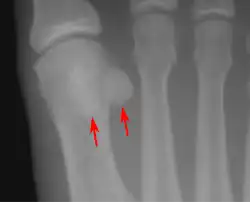

![]() Sesamoid bones at the distal end of the first metatarsal bone of the foot. | |

- In the foot—the first metatarsal bone usually has two sesamoid bones at its connection to the big toe (both within the tendon of flexor hallucis brevis).[10] One is found on the lateral side of the first metatarsal while the other is found on the medial side. In some people, only a single sesamoid is found on the first metatarsal bone.